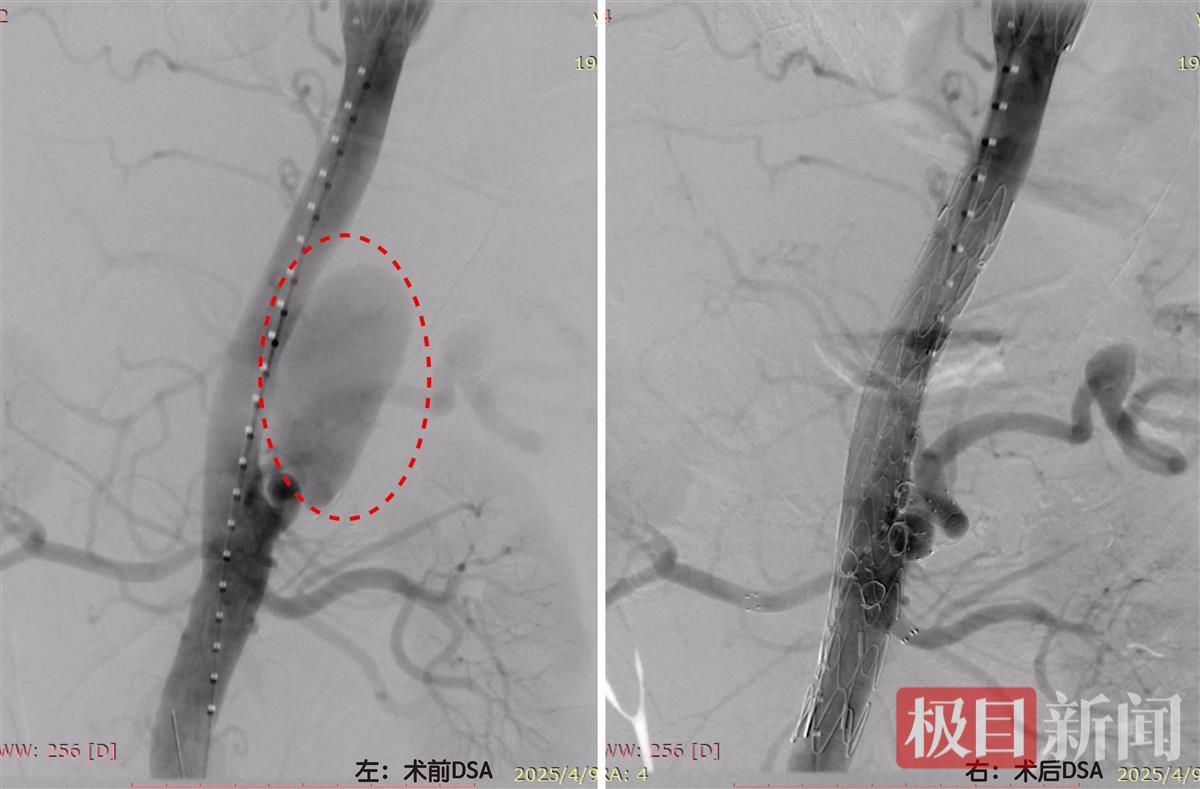

左图:术前DSA显示腹主动脉巨大夹层动脉瘤; 右图:术后DSA造影见腹主动脉夹层动脉瘤消失,四支分支血管供血正常

这颗藏匿于体内的“炸弹”,不仅瘤壁“薄如蝉翼”,剧烈咳嗽都可能引发破裂,更棘手的是,它恰好卡在供应肝脏、脾脏、肠道和双肾的4根重要动脉处。

传统治疗手段陷入两难困境:若常规植入腹主动脉支架隔绝瘤体,4根“生命通道”将被完全封堵,导致多脏器坏死;而开放手术需要开腹切除动脉瘤置换人工血管,创伤大、恢复慢,对80岁高龄老人来说风险极高。